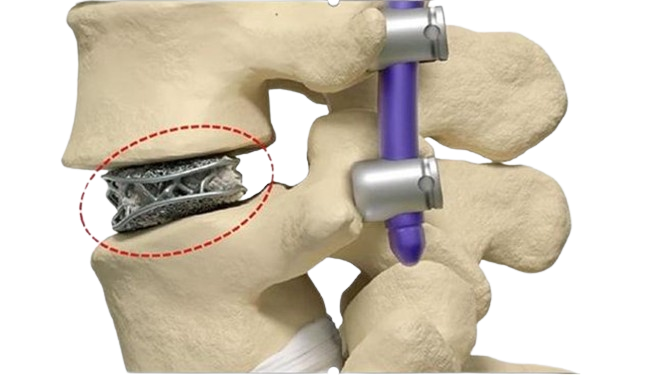

Patient-specific equipment and systems

Patient-specific equipment (such as hearing aids) and implants (such as artificial limbs, cranial plates, and even heart valves) are increasingly turning to 3D printing for rapid modification and accelerated development.

There are design advantages too: 3D printed silicone heart valves have the perfect match that rigid, commonly designed heart valves simply can’t. For implants such as titanium artificial joints or cranial plates, the services of 3D printing companies can produce intricate and porous surfaces that make patients’ bodies less likely to resist implants.